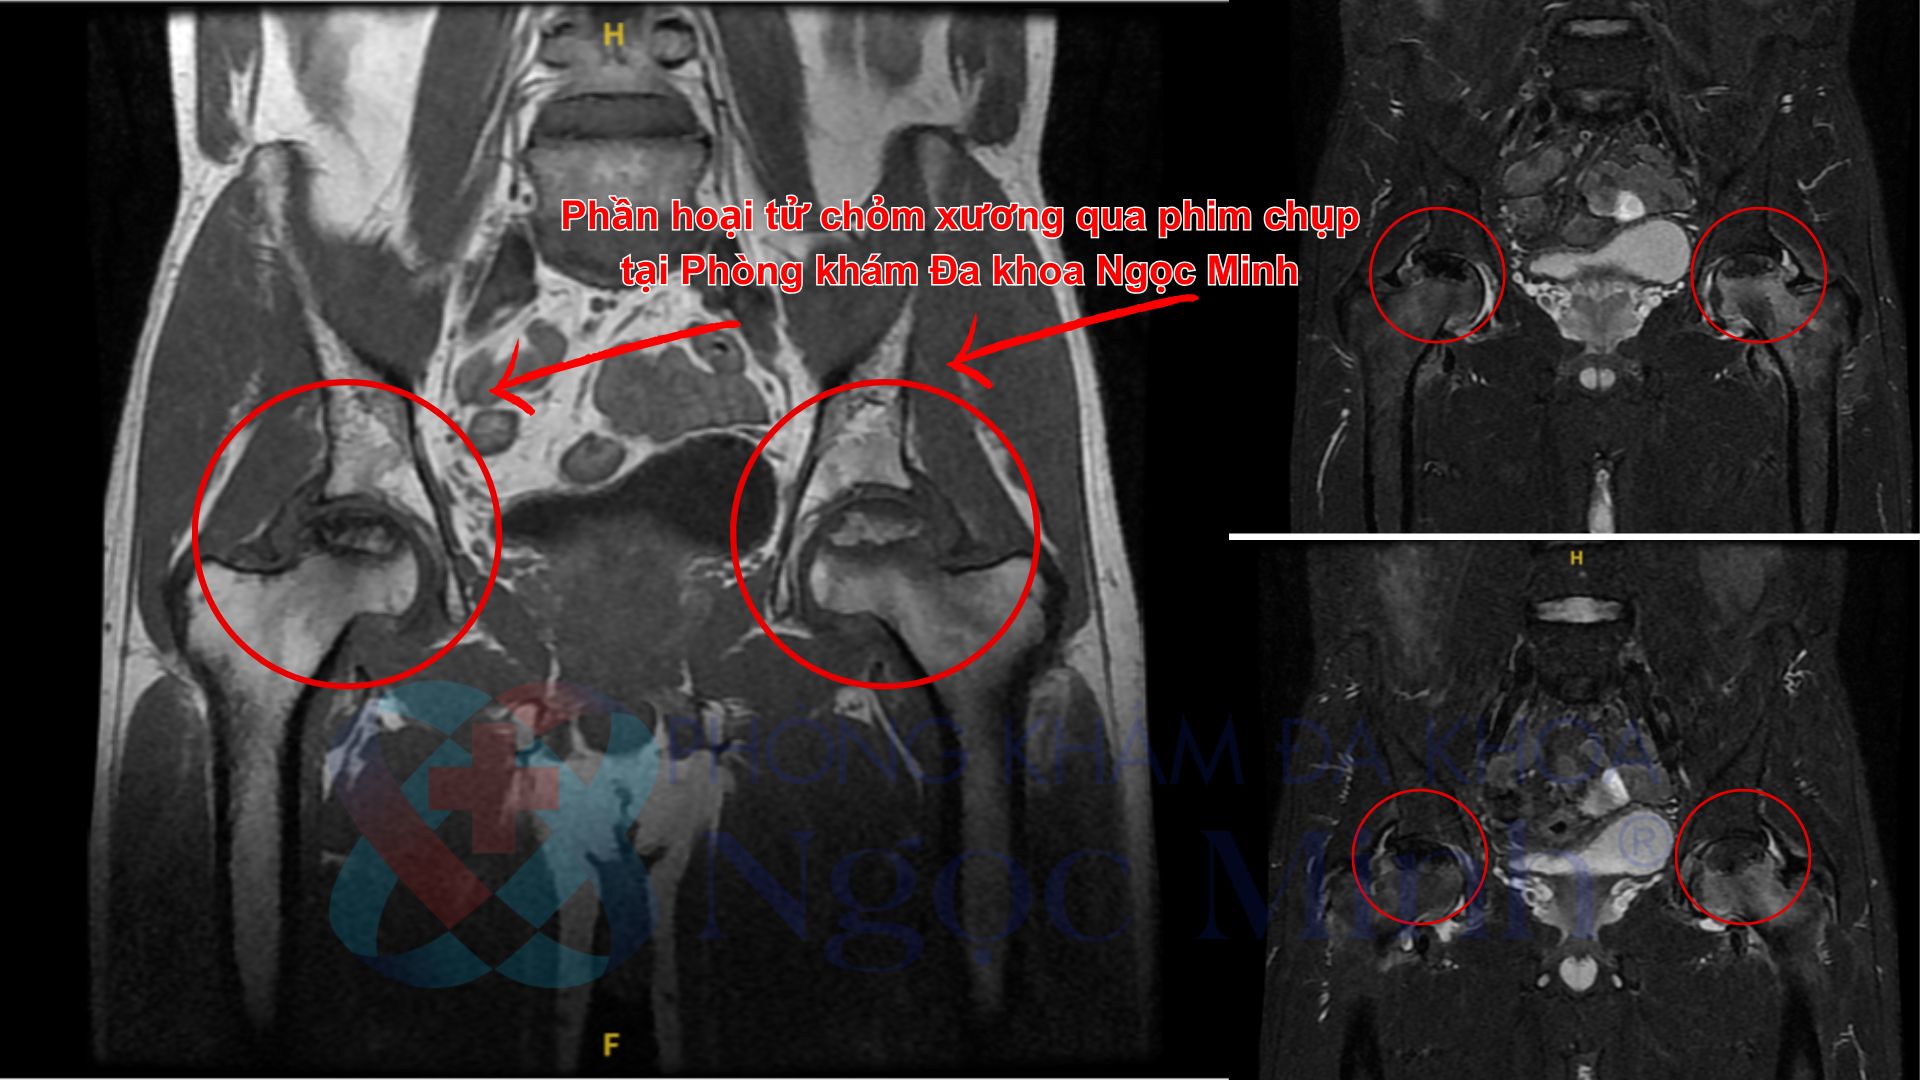

Kết quả thăm khám và chụp cộng hưởng từ (MRI) xác định bệnh nhân bị hoại tử và xẹp lún chỏm xương đùi cả hai bên, ở giai đoạn 3C theo phân loại ARCO (giai đoạn tiến triển). BS.CK1 Lê Thị Mai - Khoa Cơ Xương Khớp cho biết: “Với mức độ tổn thương này, việc điều trị bảo tồn nội khoa không còn hiệu quả. Bệnh nhân cần được chuyển sang chuyên khoa Chỉnh hình để được đánh giá và chỉ định phương pháp phẫu thuật phù hợp”.